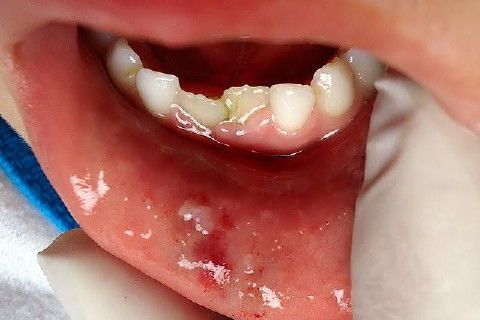

Menino de 6 aninhos sofreu um traumatismo ontem na hora do recreio, lá na escolinha aonde atendo, bateu a boquinha na mesa na hora do lanche.

Examinei-o e constatei ter sofrido apenas uma concussão.

CONCUSSÃO é o trauma dentário menos agressivo que se apresenta.

Sem consequências aparentes ao exame clínico, nenhum dano ao tecido dentário, com pequena agressão aos tecidos de suporte e os dentes apresentam pequena sensibilidade ao toque.

Obs: As duas últimas fotos foram tiradas hoje (24 hs depois).